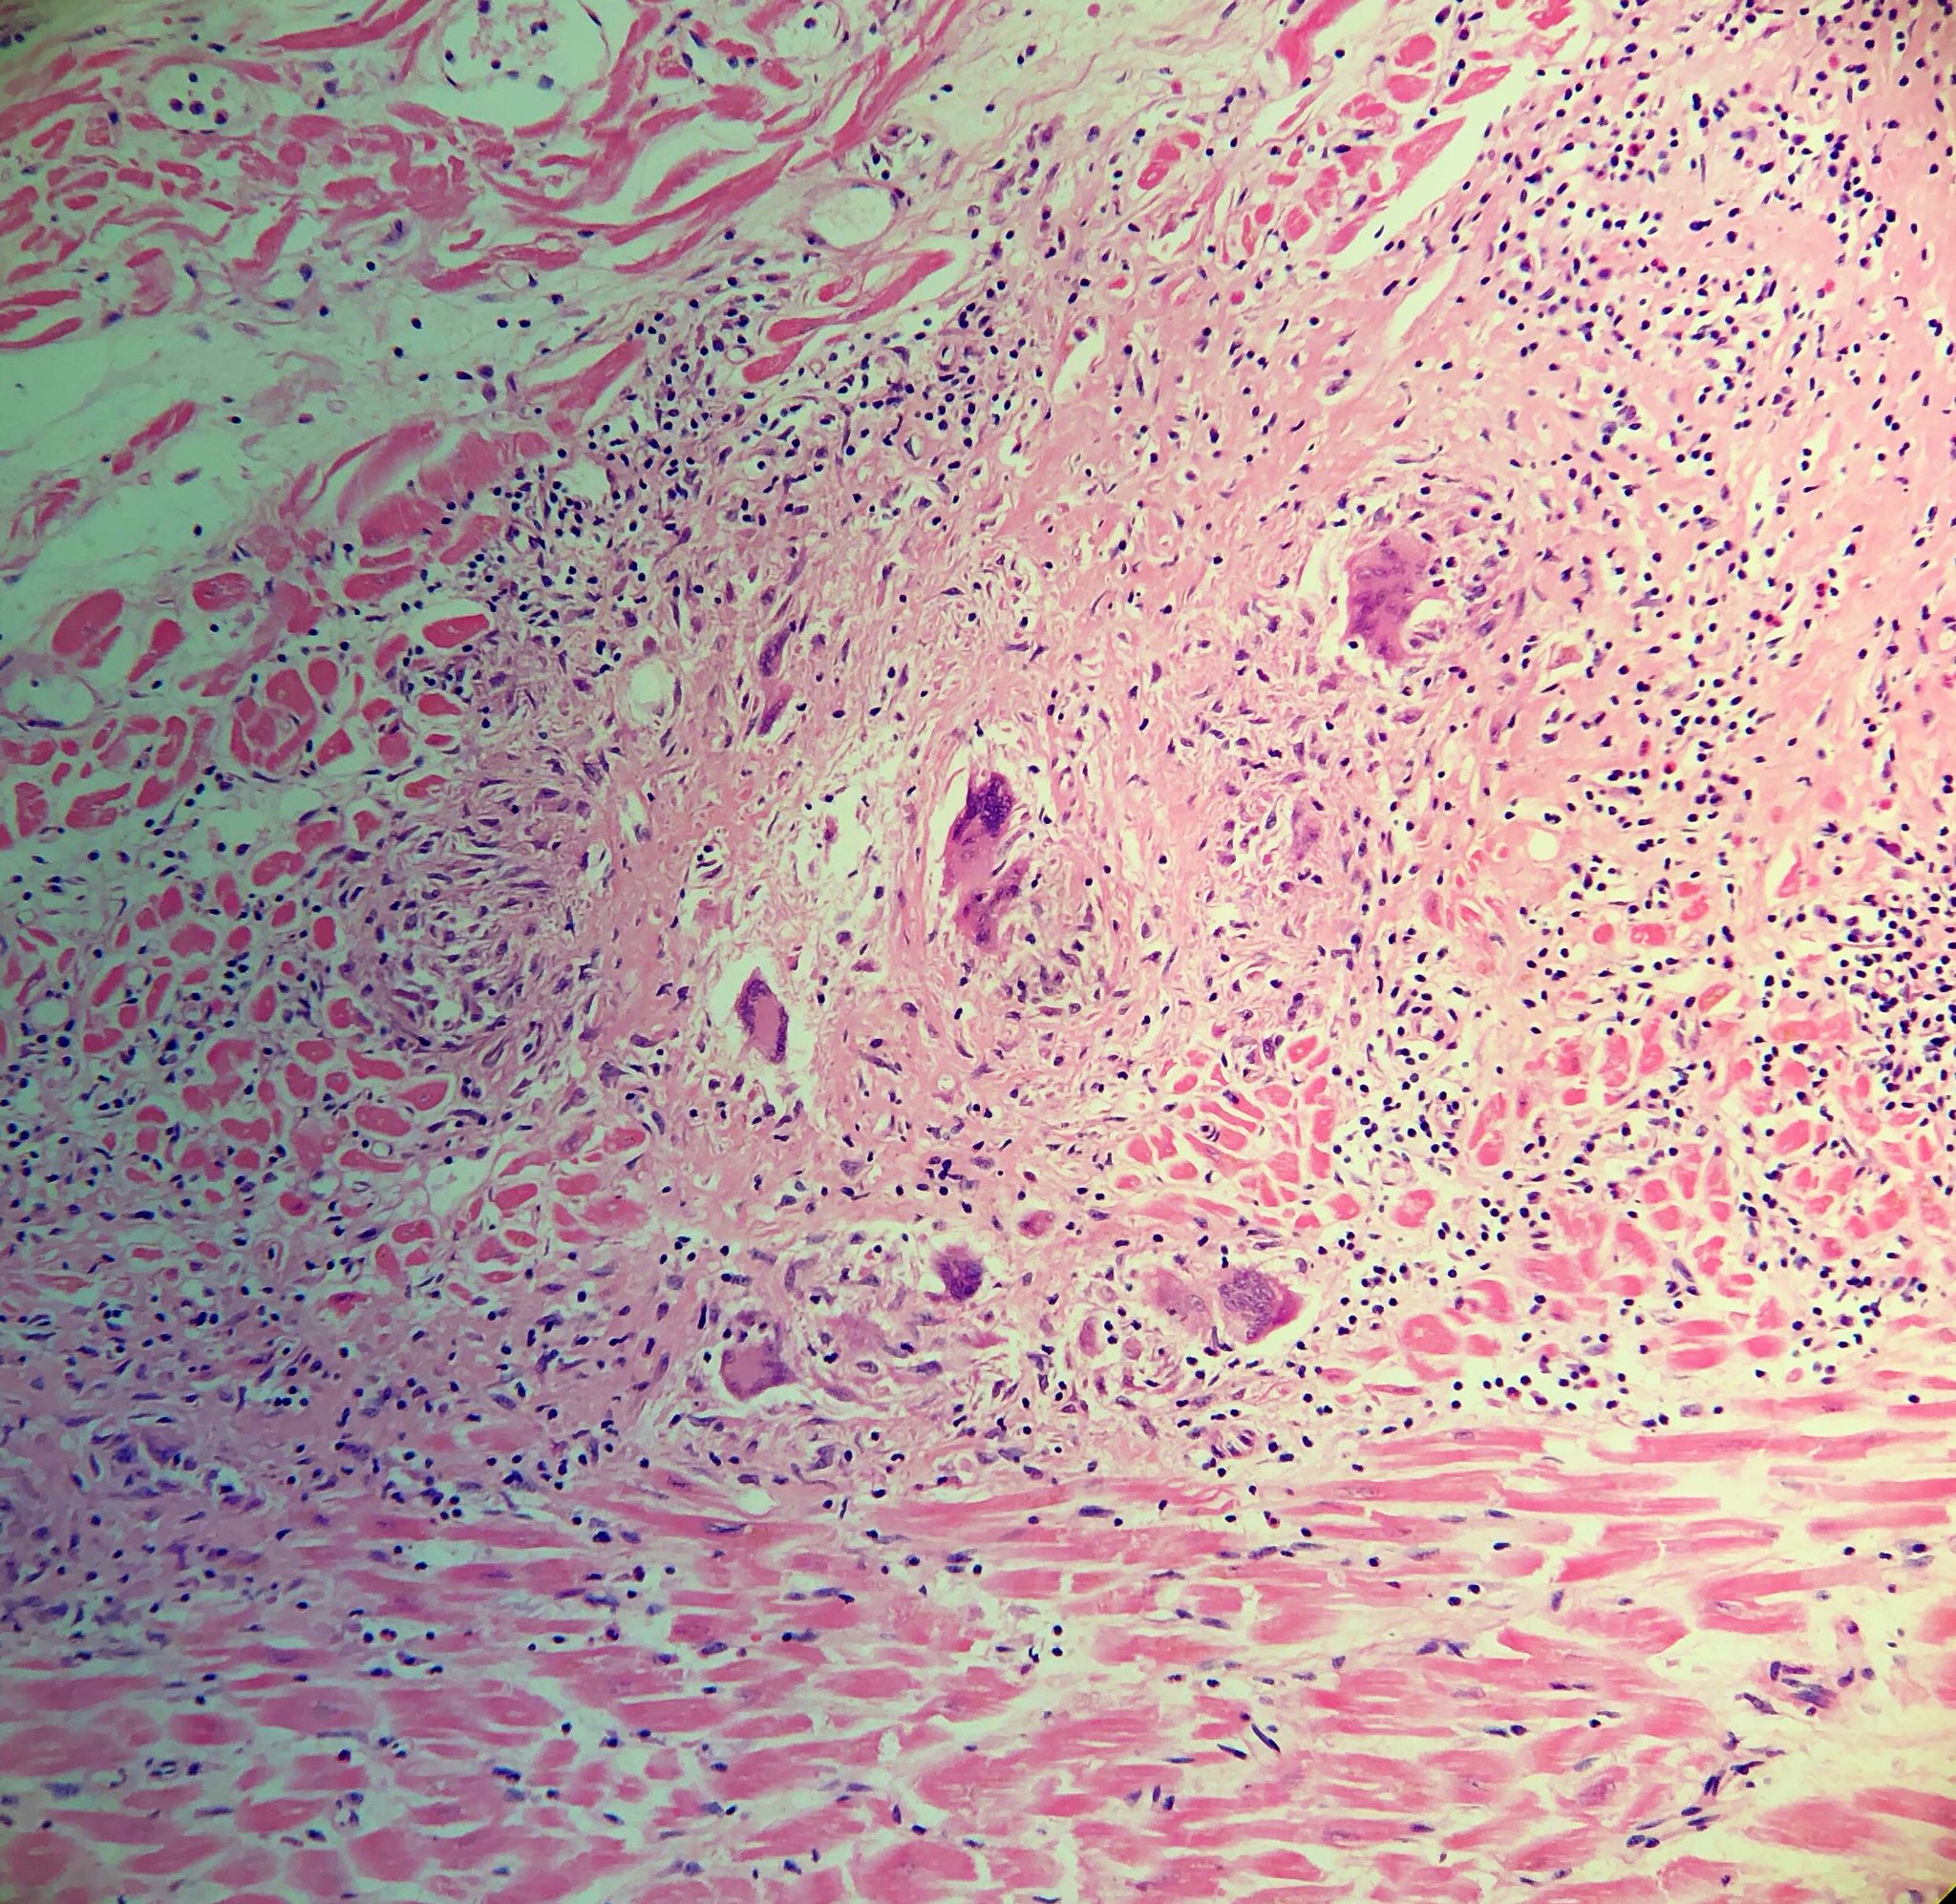

Межуточный миокардит: гистологические исследования